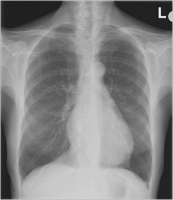

Thorax-Röntgen

Abbildung 2: Thorax-Röntgen: linksventrikulär betontes Herz, keine Stauungszeichen, Aortensklerose, keine Infiltrate, dorsal adhärenter Recessus, suspekte Zeichen einer Rechtsherzbelastung.